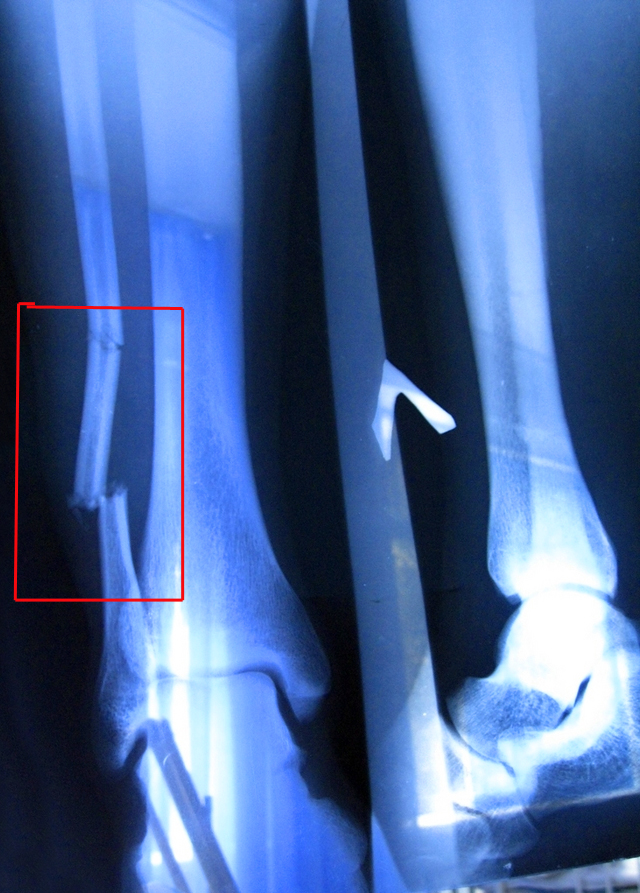

Наиболее неприятным является открытый перелом нижней части большой берцовой кости. Лечение открытого перелома основывается на скелетном вытяжении. В случае неудачного лечения, необходимо применить остеосинтез (внутренний) при помощи винтов и пластин.

В настоящее время большинство хирургов используют интрамедуллярный метод лечения переломов большеберцовой кости. В ходе этой процедуры внутрь большеберцовой кости вводится специально разработанный металлический стержень (штифт). Штифт проходит через место перелома, фиксируя его в нужном положении. Для стабилизации штифта с обоих концов (сверху и снизу) используются винты.